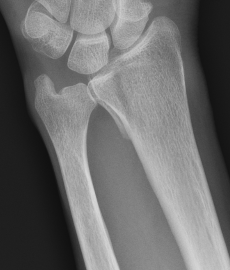

Distal radius fracture with shortening and dorsal tilt

Articular incongruency > 2 mm

Sigmoid notch disruption and DRUJ instability